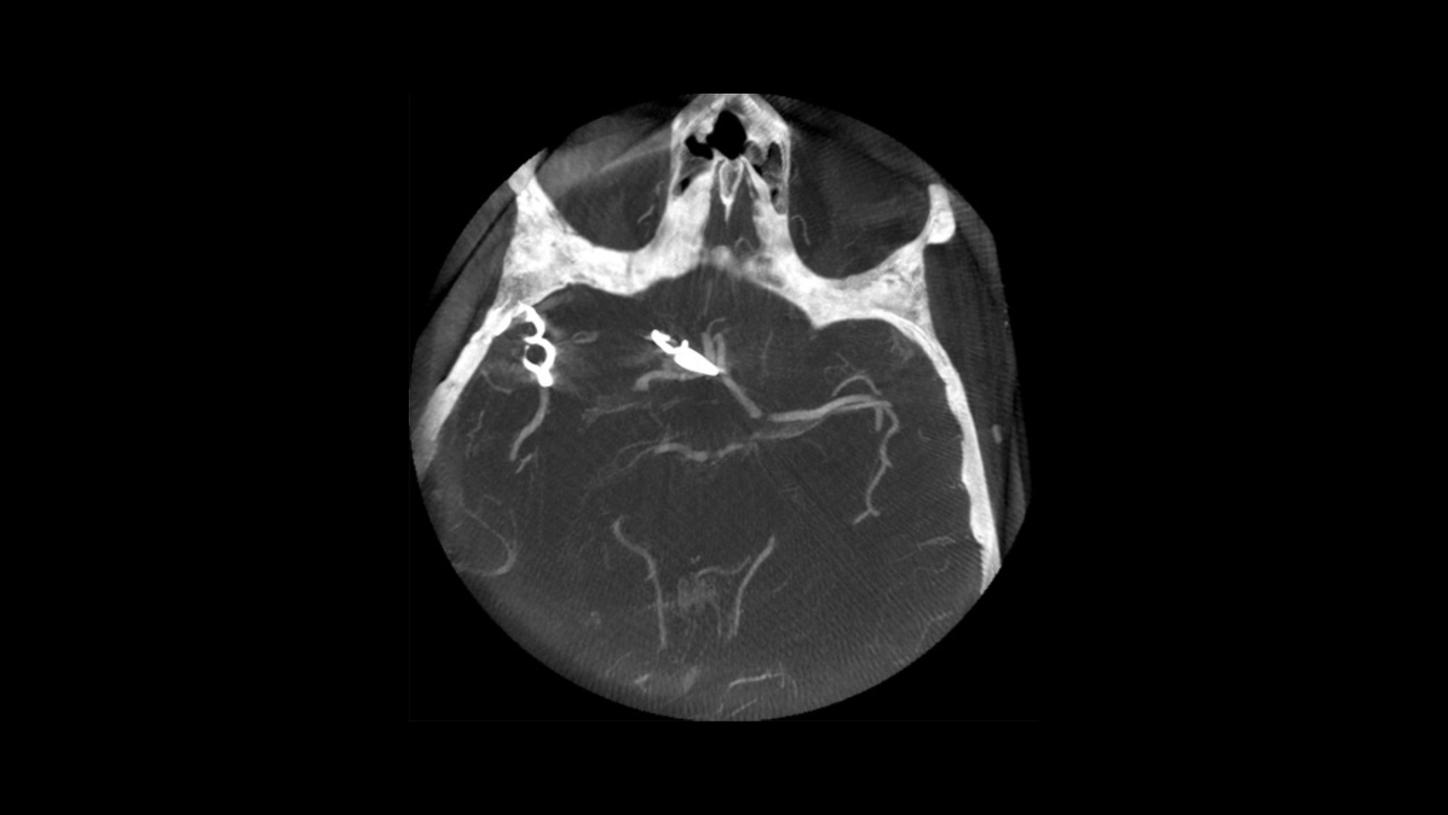

Native syngo DynaCT Sine Spin

syngo DynaCT Sine Spin improves the image quality of cranial Flat-Detector CT (FDCT) scans, especially in the posterior fossa and the basal part of the skull. syngo DynaCT Sine Spin reduces artifacts caused by bony structures.